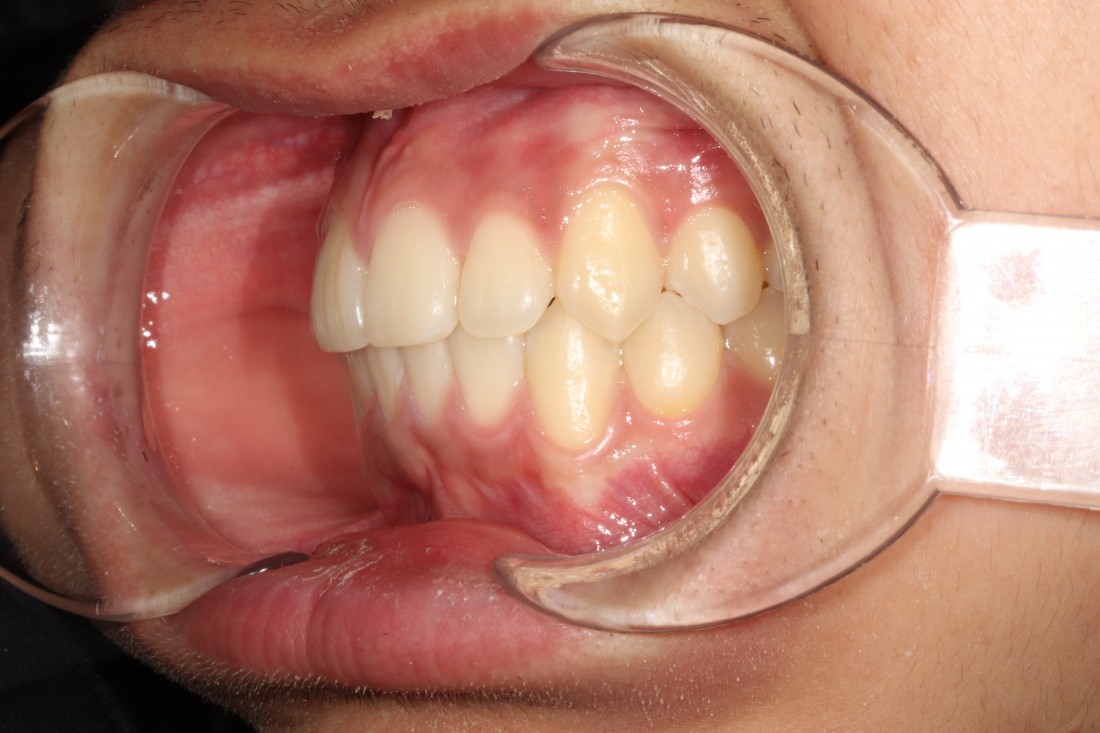

대한교정학회 치료지침 상

유치에서 영구치로 바뀌는

혼합치열기 (만5세~12세)에

부정교합 개선을 빠르게 해주는 것이 권장됩니다.

성인이 된 이후에도

과개교합을 방치하게 되면

앞니가 많이 마모되게 되며,

사각턱이 생길 수 있으며

무엇보다 교합이 맞지 않기 때문에

시간이 지날수록 턱관절장애를 유발하게 되어

빠르게 개선해주는 것이 좋습니다.